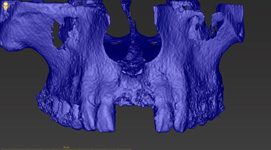

Jedná se o externí plánovací program, spojený se zubní laboratoří a frézovacím centrem, který využívá dat získaných z 3D rentgenu čelisti, otisku zubů a dásně (scanu zubů a dásně) a finálního návrhu protetické náhrady. Tento program umožňuje tříprostorovou počítačovou simulaci při plánování pozic implantátů. Součástí programu je i databáze, ve které mohou být uloženy všechny typy implantátů od všech výrobců, včetně jejich délek, průměrů i tvarů.

Lékař si vytvoří všechny typy zobrazení potřebných pro naplánování – tedy 2D snímky (panoramatický), příčné řezy i 3D model.

Vidí zde i důležité anatomické útvary – čelistní dutinu, průběh nervu atd. Po proměření množství kosti – šířky i výšky vybere z databáze vhodný typ implantátu a umístí ho do požadované lokality. Ihned vidí jeho pozici ve všech 3 rovinách a na všech snímcích i 3D modelu. Může upravovat podle potřeby jeho pozici, sklon atd.

Všechny vybrané a správně umístěné simulované implantáty se ukládají do „počítačové karty“ pacienta s jejich pozicí, délkou, průměrem, typem i sklonem. V programu také lékař navrhuje chirurgické šablony pro řízenou nebo navigovanou implantaci. Lékař i pacient tedy ještě před vlastní operací vidí, jak by mělo ošetření probíhat a vypadat.